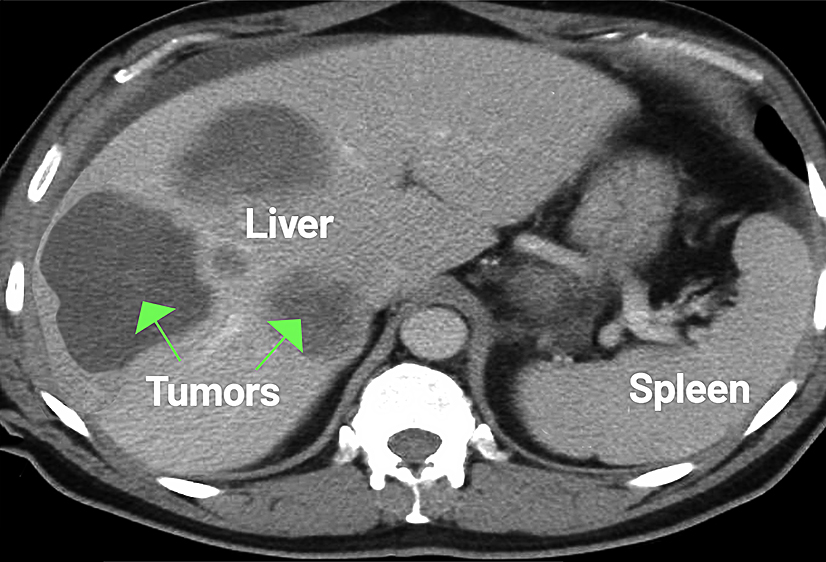

Advanced imaging is essential for assessing adrenal tumors and determining whether cancer has spread beyond the adrenal gland. CT scans, MRI, and PET imaging help evaluate tumor size, shape, and involvement of nearby structures, offering critical information for surgical planning. Certain imaging features can also help distinguish benign adrenal masses from those that are more suspicious for adrenocortical carcinoma.

- CT scan

- MRI

- PET scan

Imaging helps determine tumor size, involvement of nearby structures, and whether the cancer has spread.